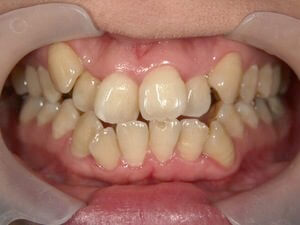

虫歯の治療、矯正の相談をご希望され来院されました。お口の中を診査(レントゲン写真、口腔内写真、視診)させていただいたところ、虫歯については問題なくきれいに歯磨きされているようでした。 正面から見るとジグザグしており、お口 […]

全体的な歯並びの矯正治療を行いました。治療期間は3年間。

ジグザグの歯並びを気にされてご来院されました。. 見た目の問題も大切ですが、それ以上に清掃がしにくいために虫歯・歯周病に非常になりやすく、不正咬合(良くないかみ合わせ)は顎の関節に負担をかけてしまい顎関節症を引き起こす可 […]

歯の大きさに対する顎の大きさのスペース不足により歯が並びきらず、ジグザグの歯並びおよび上の前歯が出っ歯になっていました。 左右4番の歯を抜歯することにより歯を並べるスペースを確保し、歯並びを揃えました。 全体の歯並びが綺 […]